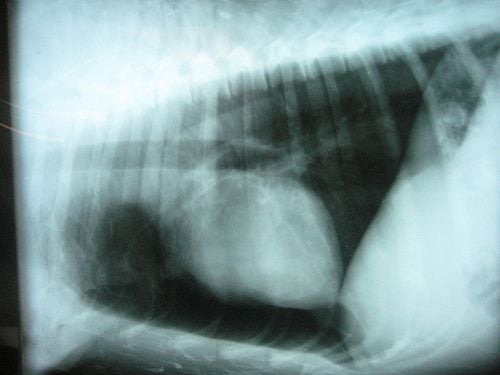

Bélrészletek előesésekor a mellkas felett bél hangok is hallhatóak. Kopogtatásos vizsgálattal a mellkason tompulat kopogtatható ki; minden esetben meg kell azonban vizsgálni, nem felhalmozódott folyadék okozza-e a kopogtatási hang tompulatát. A vizsgálat részeként két síkban röntgenfelvételt kell készíteni, így megállapítható, melyik tüdőfél beteg. A sérv helyeinek meghatározása érdekében kontrasztanyagot juttatunk a gyomorba és a belekbe. Baleseteknél mindazonáltal leggyakrabban jobb oldalon szakad át a rekesz. Ha a repedés nem nagy, és szélei gyorsan összetapadnak, akkor a tünetek már néhány nap múlva megszűnnek. Ilyen esetekben kivárhatjuk a gyógyulást, messzemenően kímélni kell azonban a kutyát mindenfajta megerőltetéstől. Nem kaphat gázképződést okozó táplálékot, és naponta többször kisebb mennyiségekkel etessük. Fennáll azonban a veszély, hogy túlerőltetés vagy akár egy enyhe lökés hatására a repedés ismét felszakad; a légzés és a vérkeringés hirtelen összeomlása az állat halálát is okozhatja. A teljes és biztos gyógyulás csak bonyolult műtéttel érhető el. Az ártalmatlan tünetek közé tartozik a rekeszizom összehúzódása által okozott csuklás. Különösen fiatal kutyáknál gyakori, többnyire hideg inger vagy izgalom váltja ki. Röntgenfelvétellel sem deríthető ki a csuklást kiváltó ok, de hosszabb ideig – átvilágítással – szemlélve megfigyelhetjük a rekesz mozgását. Kezelésként általában elegendő, ha elvonjuk a kutya figyelmét és megpaskoljuk a mellkas oldalát. Görcsoldó szerek, enyhe nyugtatók és E-vitamin adása általában hatásosnak bizonyul.